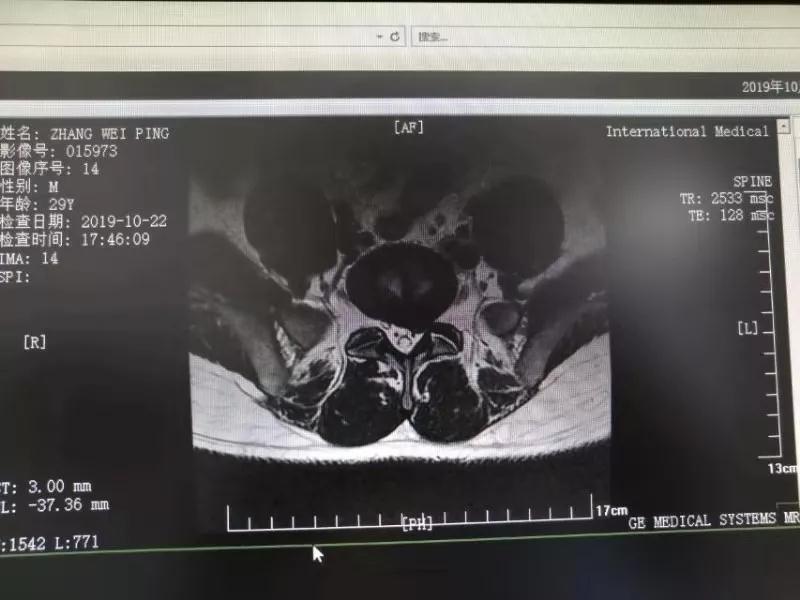

10月25日,29歲的患者小張了解到西安國(guó)際醫(yī)學(xué)中心骨科醫(yī)院專家云集,一大早便在家人的陪同下,來(lái)到西安國(guó)際醫(yī)學(xué)中心骨科醫(yī)院就診?!拔已闯掷m(xù)2年多,最近感冒后腰痛癥狀明顯加重了?!毙埫媛犊喑?,因?yàn)殚L(zhǎng)期腰痛、左下肢放射性疼痛,她晚上睡覺(jué)不能平躺,經(jīng)常疼得睡不著,需要口服止痛藥物才能有所緩解。走路走不了多遠(yuǎn)就開始腿抽的疼,嚴(yán)重影響到工作和生活。

結(jié)合患者的檢查以及年齡情況,王自立副院長(zhǎng)推薦讓專門研究椎間孔鏡技術(shù)王雄勛主任給小張做微創(chuàng)的椎間孔鏡手術(shù)。該手術(shù)創(chuàng)傷很小,不影響脊柱的穩(wěn)定性,尤其適合于椎間盤突出的年輕患者,懷著對(duì)骨科醫(yī)院專家的信任,小張與家人商議后,接受手術(shù)治療。